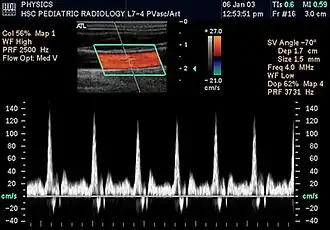

Kidneys

Doppler ultrasonography is widely used in renal ultrasonography. Renal vessels are easily depicted by the color Doppler technique in order to evaluate perfusion. Applying spectral Doppler to the renal artery and selected interlobular arteries, peak systolic velocities, resistive index, and acceleration curves can be estimated (Figure 4) (e.g., peak systolic velocity of the renal artery above 180 cm/s is a predictor of renal artery stenosis of more than 60%, and a resistive index, which is a calculated from peak systolic and end systolic velocity, above 0.70 is indicative of abnormal renovascular resistance).[12]